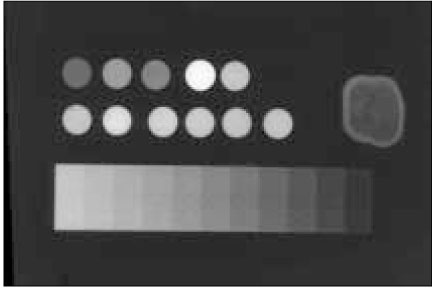

Figure 1

A radiograph showing the radiopacities of each experimental material and dentin and their equivalence to those of the aluminum step wedge.

Figure 1 A radiograph showing the radiopacities of each experimental material and dentin and their equivalence to those of the aluminum step wedge.